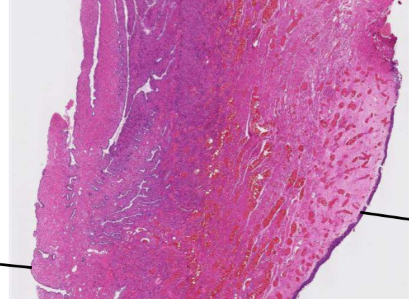

de l’Ext vers l’intérieur dans cette lame de l’uretère en HE

• adventice(rose)

• musculeuse (mauve)

• muqueuse (violet=urothélium)